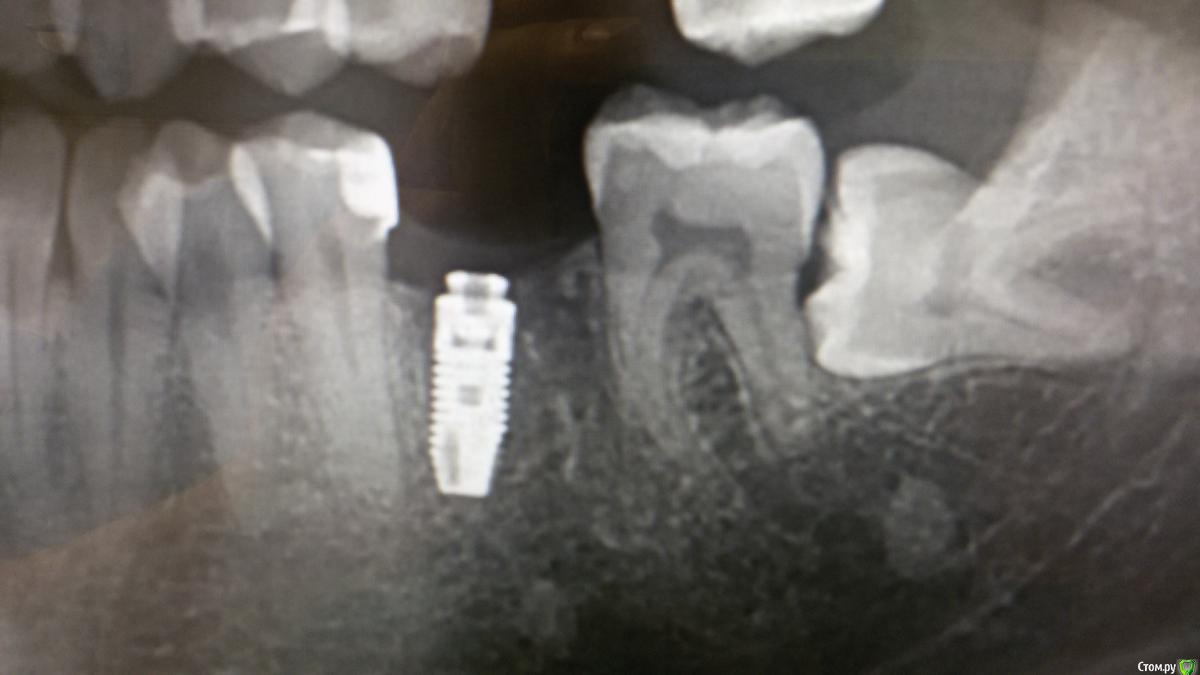

El_cucuy Опубликовано 22 января, 2020 Поделиться Опубликовано 22 января, 2020 (изменено) 1) поставить низкую заглушку, подшить сверху трансплантат под лоскутки 2) не делать ничего до интеграции, решать вопросы на втором этапе Доброго времени суток , доктора . По состоянию на 20 декабря , вот такая картина , нужно ли подсаживать трансплантат? Изменено 22 января, 2020 пользователем El_cucuy Ссылка на комментарий

El_cucuy Опубликовано 22 января, 2020 Поделиться Опубликовано 22 января, 2020 (изменено) нужны фото. И создавайте свои темы, а не засоряйте чужиеТот же кейс , добавил спустя 2 месяца Изменено 22 января, 2020 пользователем El_cucuy Ссылка на комментарий

Дмитрий Л. Опубликовано 26 января, 2020 Поделиться Опубликовано 26 января, 2020 Я бы не подсаживал, вроде 3 мм есть. 1 Ссылка на комментарий

red_butler Опубликовано 26 января, 2020 Поделиться Опубликовано 26 января, 2020 не вижу смысла работать с десной Ссылка на комментарий